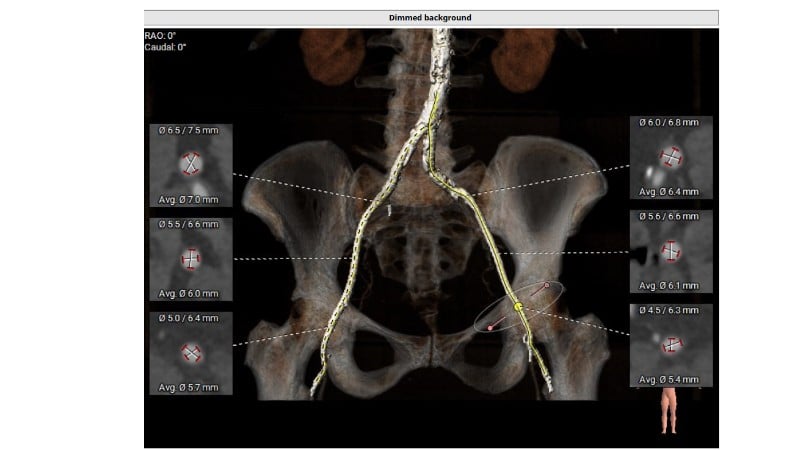

Discover how thoughtful index valve selection and implantation techniques can shape the long-term management of patients undergoing TAVI. This PCR London Valves 2025 session highlights treatment considerations for low- and intermediate-risk patients, explores how valve choice affects the feasibility of future interventions, and examines strategies to achieve optimal and durable clinical outcomes. Follow real patient case with imaging analysis, hemodynamic insights in small annuli, and discussions on planning for future revalving and coronary access.